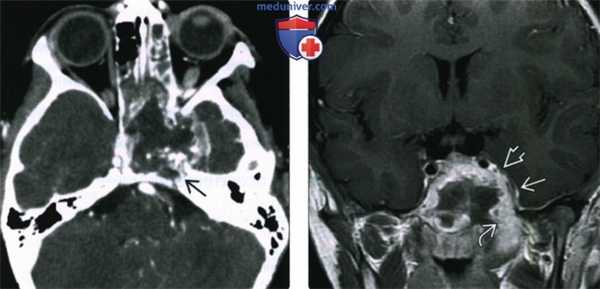

(Слева) При аксиальной КТ с КУ у шестилетнего мальчика с параличом левого лицевого нерва визуализируется большая окологлоточная РМС слева с некротическими изменениями, распространяющаяся краниально с инвазией основной пазухи и средней черепной ямки, с эрозией вершины пирамиды слева.

(Справа) При корональной МРТ Т1 ВИ С+ у пациента с окологлоточной РМС определяется, что опухоль распространяется в среднюю черепную ямку путем контактной деструкции основания черепа. Определяется также поражение левого кавернозного синуса. Четкая граница с головным мозгом позволяет предположить отсутствие интракраниального распространения.